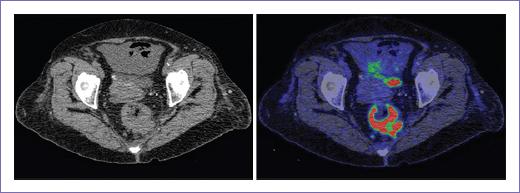

Figura 5 Metástasis en sacro derecho hipermetabólica en paciente con antecedente de adenocarcinoma de colon derecho, no visualizada por tomografía computarizada.

En la evaluación de metástasis a distancia (M), la PET-CT identificó tres pacientes M1A, dos M1B y uno M1C, mientras que la TC identificó dos pacientes M1A y el mismo número de pacientes para la estadificación M1B y M1C. No se identificaron metástasis a distancia en nueve pacientes por PET-CT y 10 pacientes por TC (Fig. 6).

Para las lesiones pulmonares, sin embargo, la capacidad de detección para ambos métodos fue la misma. Cambió la estadificación ganglionar en ocho pacientes, de estos, cinco casos incrementaron su estadiaje y tres lo disminuyeron. Así mismo, en la evaluación de metástasis a distancia, en cuatro pacientes se produjo un incremento en estadificación.

Estos cambios en la estadificación inicial de los pacientes con CCR podrían modificar de forma potencial la estrategia en el tratamiento hasta en un 35%5.